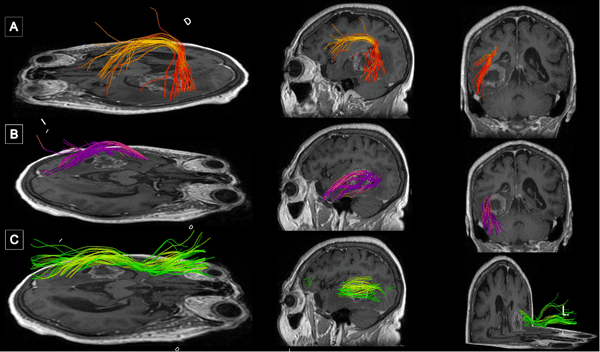

La resonancia magnética (RM) de encéfalo con gadolinio evidenció una lesión expansiva heterogénea, con áreas centrales de aspecto quístico y degeneración necrótica, localizada en la topografía temporomesial izquierda de aproximadamente 28 × 27 mm en plano axial y 29 × 26 mm en plano coronal, con realce heterogéneo tras la administración de contraste endovenoso. En secuencia de susceptibilidad magnética presentaba signos de restos de hemosiderina y/o microcalcificaciones. En el asta occipital y el atrio ipsilateral del ventrículo lateral, se evidenciaron formaciones quísticas con refuerzo periférico. La lesión descripta presentaba edema perilesional que comprometía el lóbulo temporal izquierdo y la región parietoccipital ipsilateral. Además, se observó dilatación del tercer ventrículo y ventrículo lateral homolateral. Las cisternas perimesencefálicas se encontraban libres, y las estructuras de la línea media, centradas. Las imágenes obtenidas eran sugestivas de una lesión de origen glial de alto grado (Figura 1). Se complementó con tractografía en la que se observó una disminución de la fracción de anisotropía a nivel del septum sagital con disrupción de las fibras de los tractos arcuato, frontooccipital inferior y longitudinal inferior izquierdo (Figura 2).

Figura 1. RM preoperatoria con contraste endovenoso. A y B) RM de encéfalo, cortes axial y sagital, respectivamente, en secuencia T1 contrastada, que evidencia lesión expansiva con realce heterogéneo localizada en topografía temporomesial izquierda. C) Corte axial en secuencia T2, se muestra heterogeneidad de la lesión con áreas centrales de aspecto quístico y degeneración necrótica. D) Corte axial en secuencia FLAIR que evidencia edema perilesional que compromete lóbulo temporal izquierdo y región parietooccipital ipsilateral.

Figura 2. Tractografía con reconstrucción 3D de los fascículos asociados. Disminución de la fracción de anisotropía a nivel del septum sagital con disrupción de las fibras de los tractos A) Arcuato izquierdo. B) Frontooccipital inferior izquierdo. C) Longitudinal inferior izquierdo.

Figura 6. Comparación de resonancias magnéticas pre y postquirúrgicas. A y B) RM prequirúrgica de encéfalo, cortes axial y sagital, respectivamente, en secuencia T1 contrastada, se evidencia lesión expansiva con realce heterogéneo localizada en topografía temporomesial izquierda. C y D) RM de encéfalo con gadolinio realizada aproximadamente un mes luego de la intervención quirúrgica. Cortes axial y sagital, respectivamente, en secuencia T1 contrastada en la que se evidencia en región temporomesial izquierda un área de señal líquida con signos de gliosis periférica, sin evidencia de lesión tumoral residual.